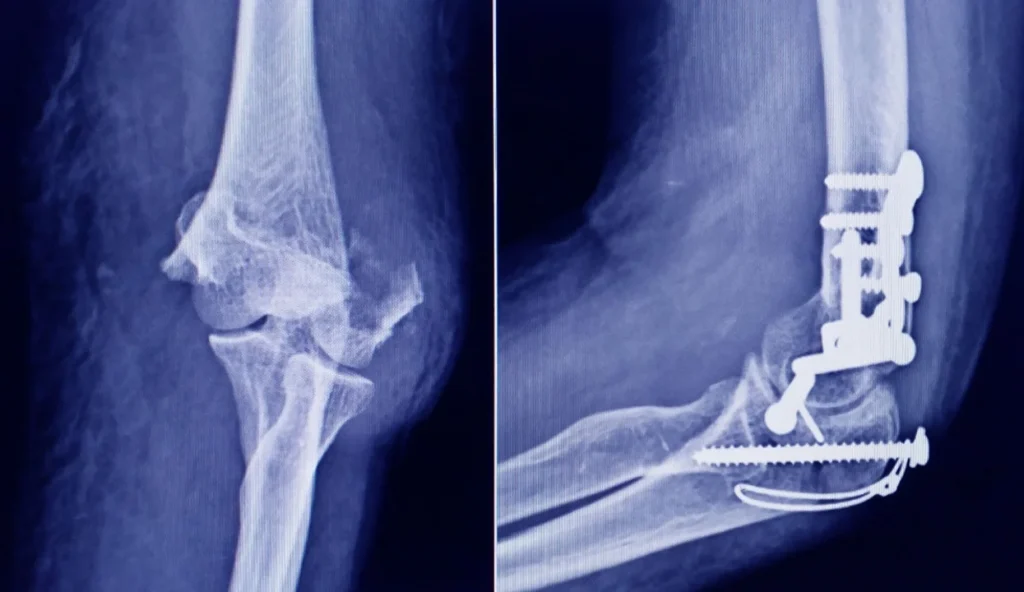

La Administración Nacional de Medicamentos, Alimentos y Tecnología Médica (ANMAT) advirtió a la población por un tornillo utilizado en cirugías traumatológicas debido a que es falso, por lo que su uso representa riesgo para la salud del paciente al que se lo implante.

Se trata de un tornillo utilizado en cirugías traumatológicas que fue detectado durante una inspección de control de mercado realizada en una ortopedia ubicada en la ciudad de San Miguel de Tucumán.

Dicho tornillo es producido por la firma Stryker Corporation, que se encuentra registrada ante ANMAT bajo el PM 594-139. Luego de la inspección, se exhibió la muestra recolectada ante la responsable técnica de dicha empresa, quien afirmó que se trataba de un producto falsificado.

Las autoridades de la ANMAT dieron a conocer las características del producto para su advertencia: STRYKER 10 mm X 28 mm – BIOABSORBABLE – ACL INTERFERENCE SCREW – REF 234-010-067 – LOT 90905.

Según supo la Agencia Noticias Argentinas, al tratarse de un producto falsificado, se desconoce el origen, composición, seguridad y aptitud del producto mencionado, por lo que su uso representa riesgo para la salud del paciente a quien se lo implante.